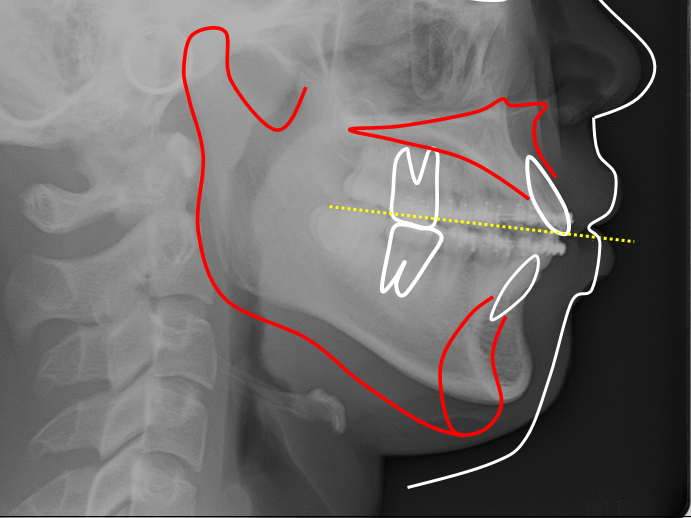

골격 원인 개방교합

개방교합의 원인은 손가락 빠는 습관, 비염이나 편도의 비대로 인한 입으로 숨쉬는 습관, 위턱의 하방 과잉성장, 턱관절 장애등 다양한 원인이 있을 수 있습니다. 원인에 따라 치료방법이 달라지므로 정확한 검진과 상담이 필요합니다.